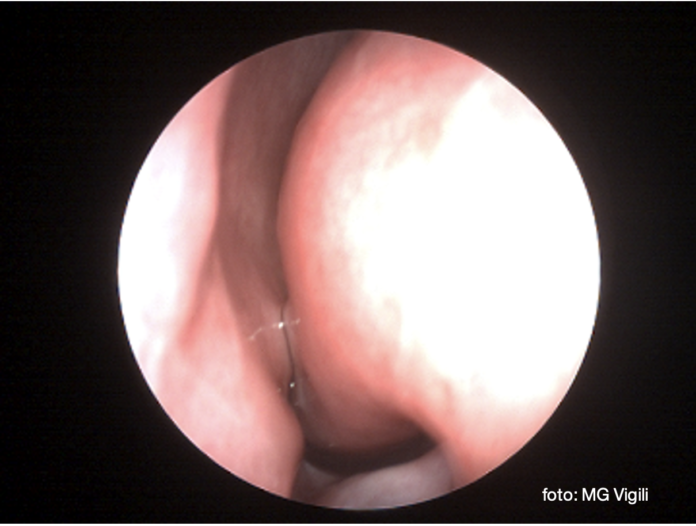

Turbinati con Radiofrequenza: approccio Endoscopico in Microchirurgia